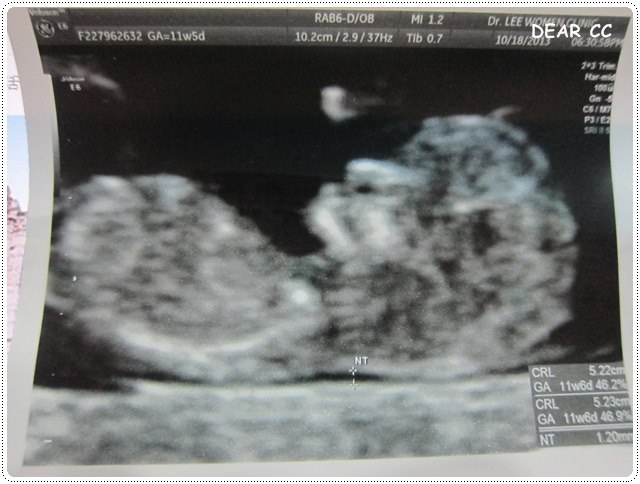

大致來說,初唐就是要檢查胎兒的頸部透明帶

可以從頸部透明帶的厚薄(越薄越好)加上媽媽的抽血推測得唐氏症的機率

蕭CC也很配合,在照頸部透明帶的時候,有乖乖躺好

讓醫生量了好幾次,取平均值,1.2mm

根據醫生解釋,是低風險

不過還要配合抽血報告才比較準確